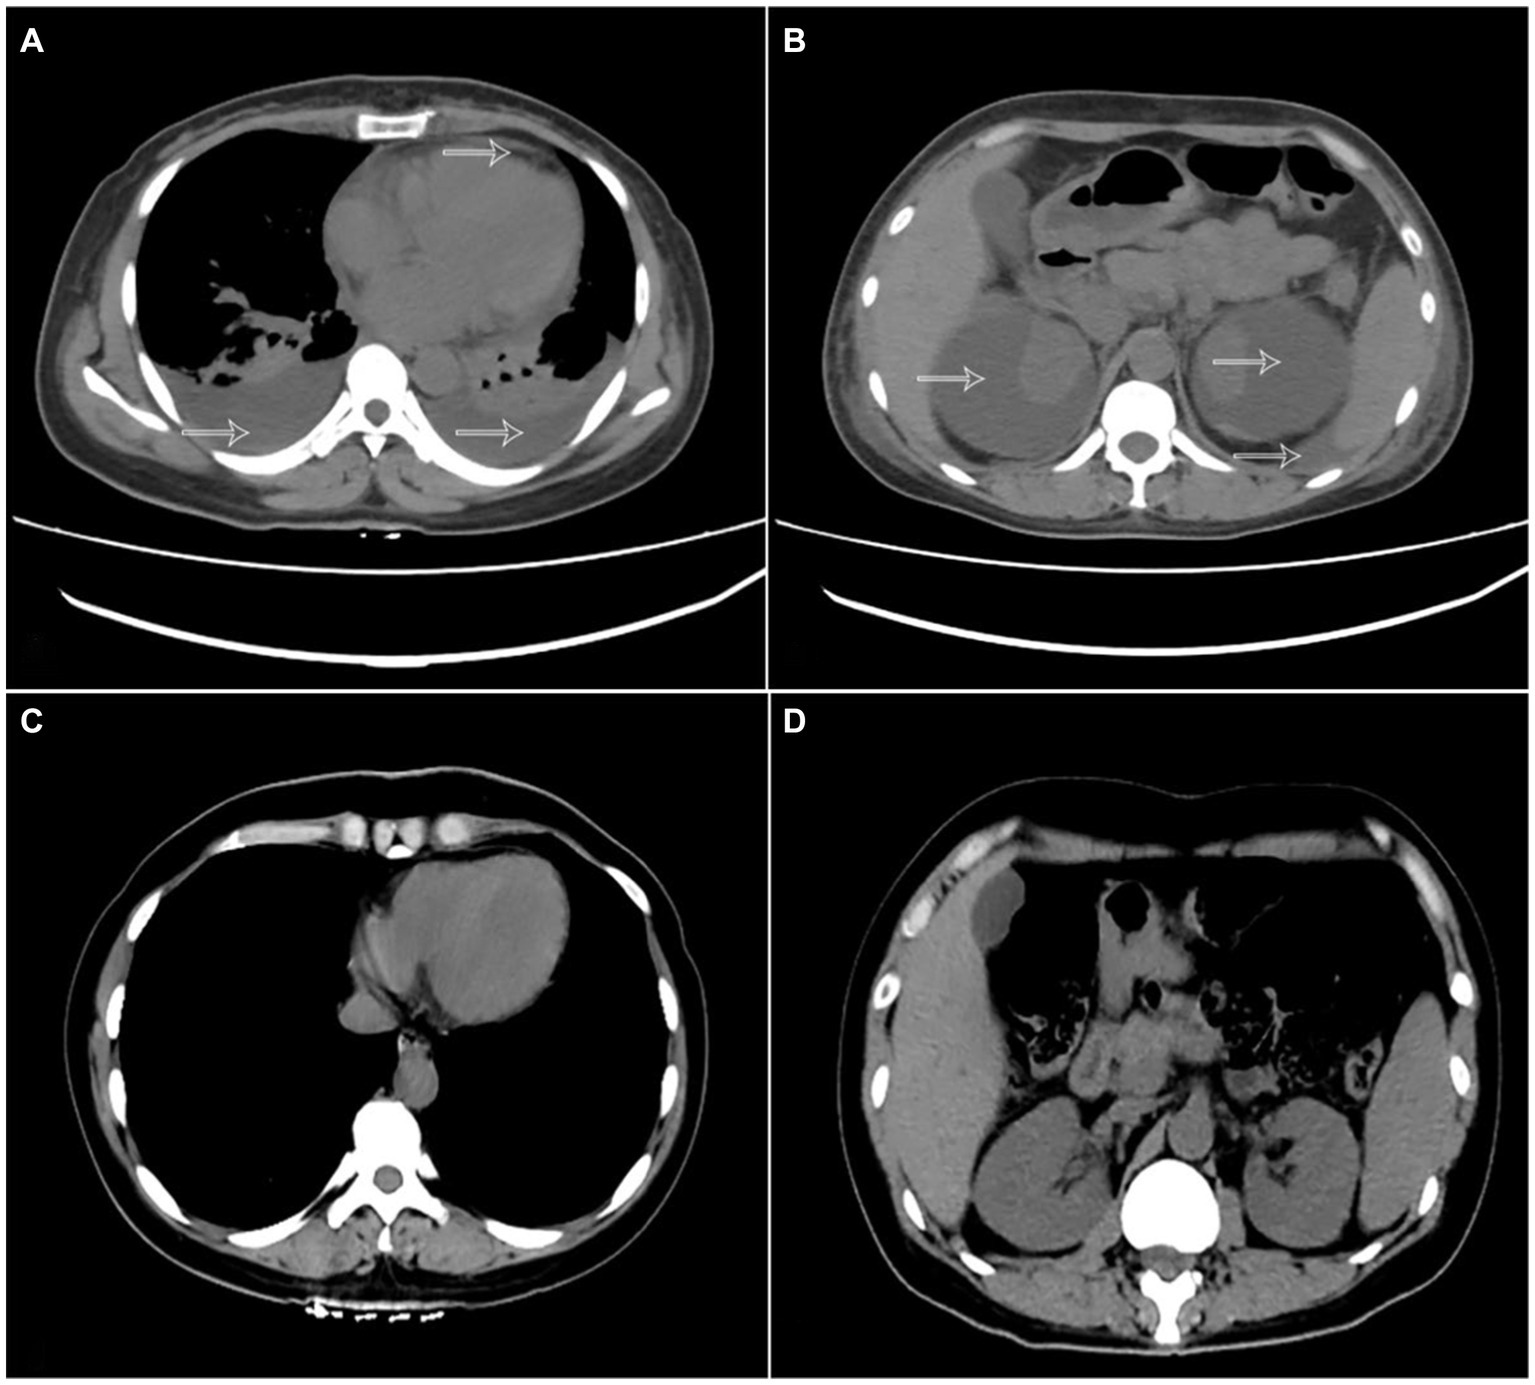

A 40-year-old woman was admitted to the hospital with bilateral lumbar and abdominal pain for 1 month, which aggravated for 4 days. The patient denied a history of trauma and surgery, a history of chronic diseases such as hypertension, diabetes, and heart disease, a history of infectious diseases such as hepatitis, tuberculosis, and typhoid fever, and a history of gastrointestinal and gynecological tumors, and no symptoms such as bone pain, butterfly erythematosus, or photosensitivity. Physical examination on admission were as follows: blood pressure 180/110 mmHg, breathing 29 times/min, unable to lie down or sit upright to breathe, painful face, anemia appearance, pale face, flat abdomen, abdominal tenderness, obvious in the left waist and umbilical circumference, no rebound pain or muscle tension, positive clicking pain in the kidney area and ureter walking area, and irregular mass in the bilateral rib abdomen. Laboratory tests indicated serum protein electrophoresis (−), anti-ANCA-GBM detection (−), urine Benchia protein characterization (−), hematuric amylase determination (−), anti-streptococcal hemolysin O (−), anti-nuclear antibody profile +ANA (−), alpha-fetoprotein (−), carbohydrate antigen 125 (−), immunoglobulin (−), and myocardial infarction (−). Laboratory examination: blood Creatinine: 375 umol/L, plasma albumin 30.1 g/L, hypersensitive C-reactive protein: 52.845 mg/L, blood routine: HB: 85 g/L, urine routine: 34 WBC/μl, 246 RBC/μl, NTproBNP: 12110 pg./mL. Chest CT (Figure 1A) showed double lung pneumonia, pulmonary edema, and a small amount of pericardial effusion. There was bilateral pleural effusion, the anteroposterior diameter of the right pleural effusion was about 23 mm, and the anteroposterior diameter of the left side was about 20 mm. Full abdominal CT (Figure 1B) showed bilateral renal subfascial effusion or chronic hematoma, right posterior 49 mm, left posterior 64 mm, and retroperitoneal, lower abdominal, and pelvic effusion or exudation.

Figure 1. (A) Chest CT showing bilateral pleural effusion and pericardial effusion (arrow). (B) abdominal CT shows subcapsular hematoma of both kidneys and abdominal fluid (arrow). (C,D) CT examination of the chest and abdomen 1 week after surgery indicates pericardial effusion, bilateral pleural effusion, subcapsular hematoma of both kidneys, and abdominal effusion disappeared.

After admission, an active intravenous infusion of human albumin increased the serum albumin level to 40 g/L, but the symptoms of multiple serosal effusions were not alleviated. The blood pressure remained between 180 and 200/110–120 mmHg for a long time. We contacted the cardiovascular department for an urgent consultation and the combined use of three antihypertensive drugs, but the blood pressure was still poorly controlled. Considering that it was related to renal hypertension, it was necessary to relieve renal compression in time, and “percutaneous bilateral perirenal fluid puncture and drainage” was performed under emergency local anesthesia after the exclusion of surgical conjunctivitis. During the operation, the needle was inserted around the left kidney, approximately 5 cm in length, the safety guide wire was placed, the leather sheath was indentured after expansion, and a 14F latex catheter was indentured to drain 1.2 L of dark-brown blood fluid with blood clots. Puncture drainage around the right kidney was performed using the same method. The puncture fluid was brown with high tension. A 14F latex catheter was placed, and 1.5 L of dark-brown blood fluid was drained. The patient was instructed to take absolute bed care within 1 week after surgery. CT examination of both kidneys 1 week after surgery (Figure 1C) showed that the subcapsular effusion of the right kidney was significantly reduced and the subcapsular effusion of the left kidney basically disappeared compared with the preoperative image. CT examination of the chest (Figure 1D) showed that the bilateral pleural effusion was significantly reduced and the pericardial effusion was basically reduced compared with the preoperative image. After the operation, the patient’s waist and abdominal pain improved significantly, his blood pressure gradually returned to normal, and his symptoms of shortness of breath and orthopnea gradually subsided, so the drainage tubes in the bilateral surgical area were removed. The patients were followed up 1 and 2 months after the operation, and both renal subcapsular effusion and polyserous effusion disappeared, and NTproBNP and creatinine returned to normal.